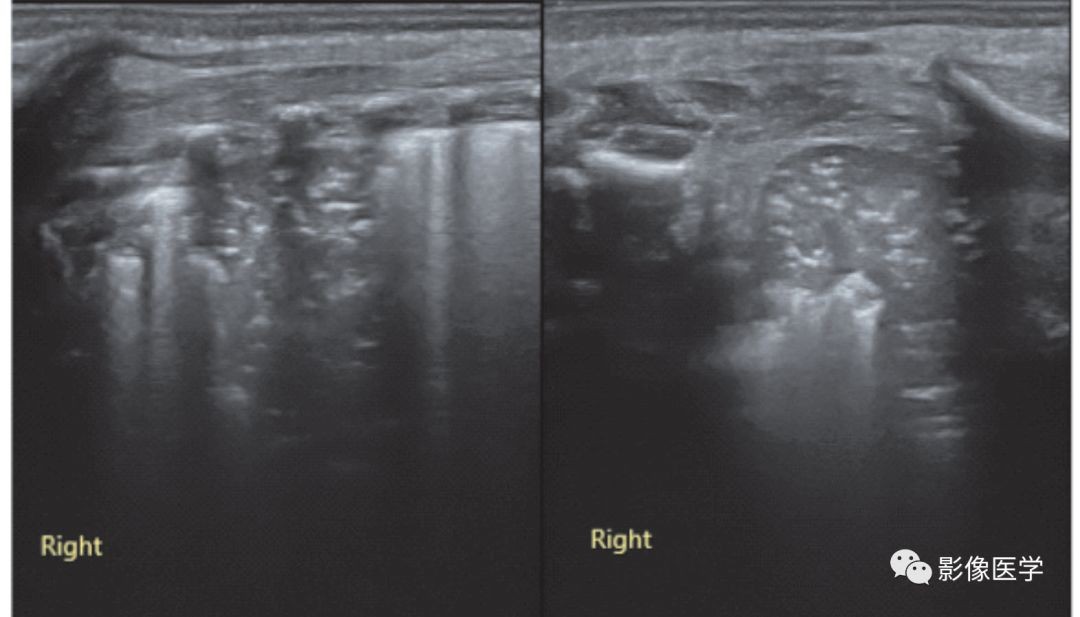

图6-12 呼吸机相关性肺炎(4)

G4P3,胎龄37周,因瘢痕子宫剖宫产分娩,出生体重3 480g。无宫内窘迫和胎膜早破,出生时无窒息。出生后3h开始呼吸困难,进行性加重伴呼气性呻吟,动脉血气分析轻度异常,肺脏超声诊断为RDS,给予呼吸机治疗。此后肺部病变逐渐减轻但并未完全恢复,故继续予以呼吸机治疗,逐渐出现血常规异常。呼吸机治疗第4天,复查肺脏超声显示右下肺累及3个肋间的实变伴支气管充气征,边界不规则(左:探头与肋骨垂直扫描。右:探头与肋骨平行扫描)。